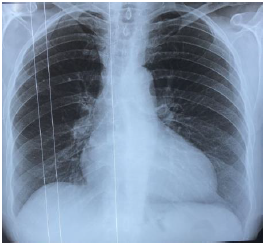

68 year-old female, born in USA, 143 pounds of weight and a 5 ft. 7 in. height; medical history of arterial hypertension, 2 years of diagnosis in pharmacological treatment with telmisartan 80mg/hydrochlorothiazide 12.5mg orally every 24hr and depression, not following the treatment. The patient arrived emergency room presenting shortness of breath with progressive minimal efforts dyspnea, orthopnea and supine hypotension. Chest x-ray: 40 % bilateral pleural effusion, mediastinal adenopathies and veiled hemidiaphragm (Figure 1). Chest tomography: cardiomegaly with global cavities increase, paratracheal adenopathies, bilateral passive atelectasis and bilateral pleural effusion (Figure 2,3).

Figure 1 Echocardiogram: dilated cardiomyophaty, left ventricular ejection fraction (LVEF) 20%, global hypokinesia, pseudonormal filling pattern, mitral moderated insufficiency, pulmonary artery systolic pressure of 57mmHg (Figure 2, 3).